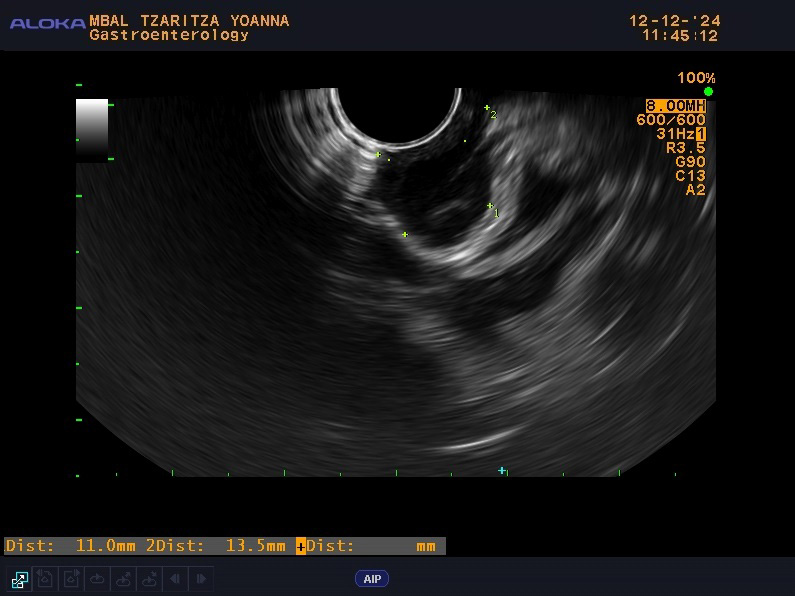

Throughout her hospital stay in our clinic, the patient exhibited normal laboratory results and no symptoms, without any other concomitant diseases or significant family history. From the physical examination (PE) the patient was slightly overweight with a body mass index (BMI)—29 without other pathological findings. The patient was scheduled for an EUS examination, which is the preferred modality for evaluating subepithelial lesions of the upper GI tract. During the EUS examination, an anechoic subepithelial lesion of the stomach was noted just below the oesophagogastric junction, corroborating the findings from the OGD. The lesion was 13.5 mm in size and displayed a typical “gut signature sign”, which is highly suggestive of a duplication cyst (Fig. 1). Given that other subepithelial lesions can appear intensely hypoechoic as lymphoma, leiomyomas, gastrointestinal stromal tumors (GIST), etc. and can mimic anechoic lesions, a CE-EUS was performed revealing enhancement confined to the wall of the lesion (Fig. 2) and confirming the diagnosis of a duplication cyst.

Fig. 2.

CE-EUS with contrast-enhancing only of the wall of the cyst and size 13.5 mm. CE-EUS was performed with 4.8 mL SonoVue—contrast-enhancing only of the wall of the cyst (the arrow) and size of the lesion—13.5 mm. CE-EUS, contrast-enhanced endoscopic ultrasound.